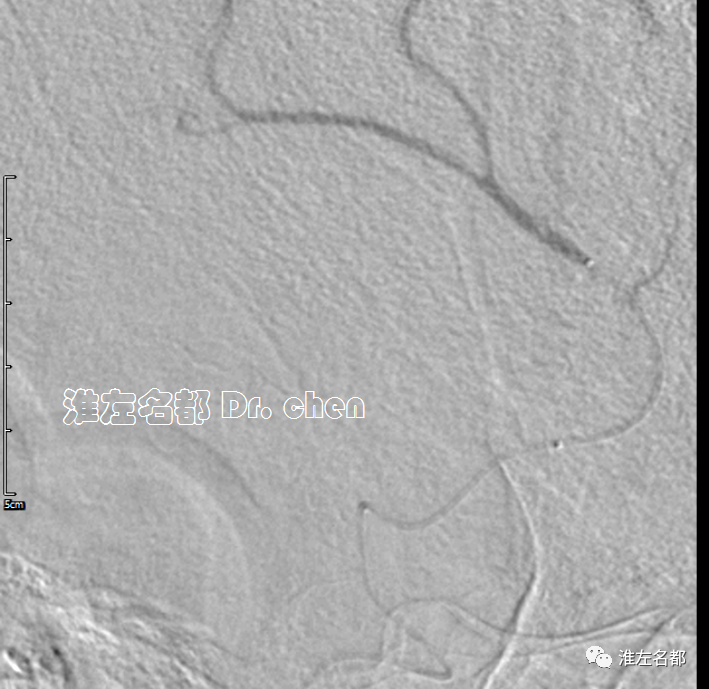

△路径过于迂曲,微导丝(Transend TM-300)进入左侧大脑前动脉后微导管(Rebar TM-18)难以跟进,将长鞘尽量进入颈内动脉增加支撑,中间导管推送到海绵窦段近端,而后微导丝通过左侧大脑前动脉闭塞段,微导管成功进入A4段,撤出微导丝,微导管造影证实位于真腔。